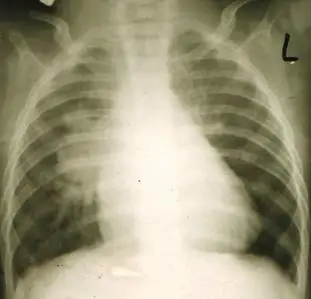

一位 6個月大男嬰因呼吸急促就醫,身體診察時在左胸前可聽到第三度 to-and-fro心雜音,於右肋下緣 4公分可觸摸到肝臟腫大,胸部 X光如圖所示。下列何者為最可能的診斷? 圖片描述

提供之胸部 X 光片顯示:

• 雙側肺門區對稱且顯著增大的圓形或卵圓狀影像,代表主肺動脈及左右肺動脈近端明顯擴張,但周邊肺血管走行清晰,並未顯著增粗,與中樞肺動脈擴張形成對比。

• 心影整體並無極度「靴型心」或「雪人徵象」,提示並非單純 TOF 或 TAPVR 阻塞型。

• 肝臟於右下緣可觸及延伸 4 cm,搭配胸片下緣肝影增大,支撐右心衰竭徵象。

上述特徵符合 APVS 典型「中樞肺動脈擴張、外周保持正常」影像表現 (pubmed.ncbi.nlm.nih.gov)。